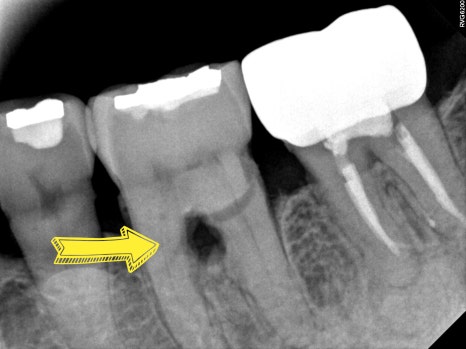

CASE 1. " 잇몸이 욱씬하고 고름이 나와요"

치주염으로 인해

치아 뿌리가 갈라지는 부위의 잇몸뼈가 소실되어

치아 지지력이 약해져 있던 케이스 입니다

염증 조직을 제거한 뒤

엠도게인 치주 재생 치료를 진행하였고,

치료 후 약 2개월 경과 관찰 시

치아 사이 잇몸뼈가

점차 회복되는 양상을 확인할 수 있었습니다